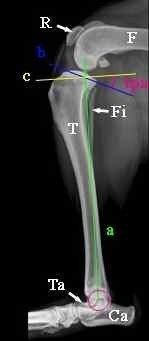

- Les traitements chirurgicaux dans la prise en charge de la dysplasie de la hanche images qui permettent d’améliorer le pronostic locomoteur du chien ainsi que sa qualité de vie.